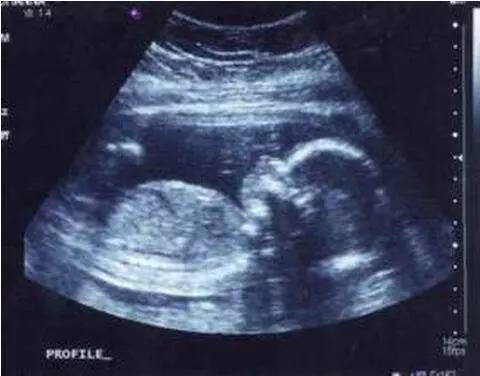

正常胎儿超声测量有许多的指标,在妊娠不同时期,可靠的测量指标有所不同,比如:孕12周以前,头臀长测量孕周最可靠;在孕12-24周时,双顶径测量值最可靠;孕28周以后,头围测量值最可靠;分娩前几周,通过胎儿的腹围测量推测胎儿体重最可靠,当胎头过大或颅内有病变时,股骨的测量值较可靠。测量这些数值与B超医生的技术有很大关系,与机器的质量也有关系,只有标准切面的测量值,才能提供标准的胎龄与体重。

最常测定的径线有头臀长(CRL)、双顶径(BPD)、头围(HC)、腹围(AC)和股骨长(FL)、肱骨长(HL)、尺骨长(UL)、径骨长(TL)、锁骨长(LL)及眼距(BN)等。

中晚期妊娠的超声测量

双顶径、枕额径与头围(BPD\DFD\HC)

这时B超单上会报告透明隔腔、两侧血脑及血脑之间的裂隙样第三脑室,同时颅骨光环是椭圆形,左右对称,胎儿头围测量值低于同龄胎儿的3倍标准差以上,是诊断小头畸形最可靠的指标之一。